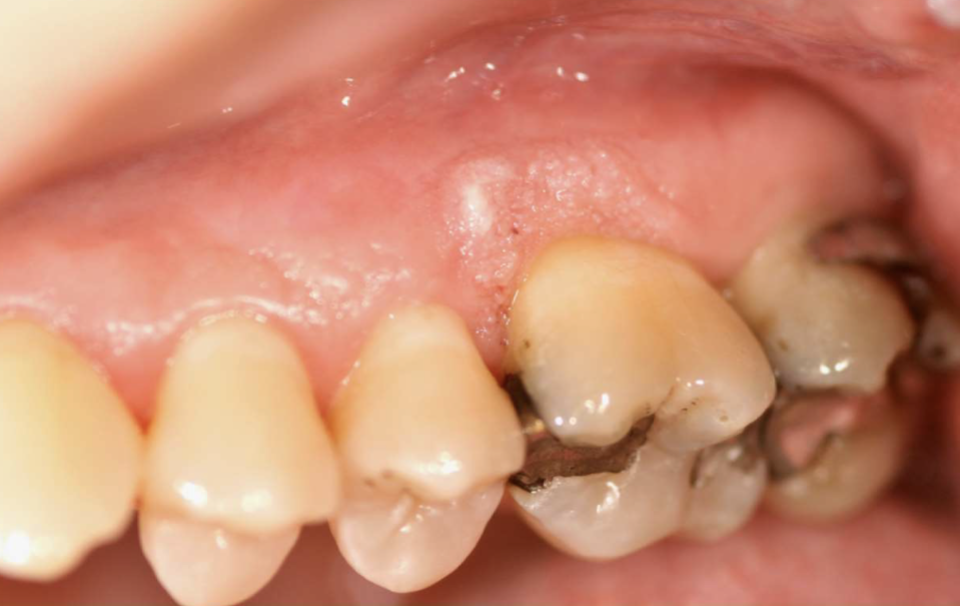

what is this

verruciform xanthoma